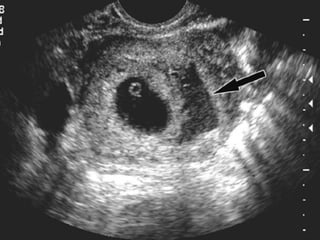

ECOGRAFIA El diagnóstico del EE se ha beneficiado de los avances producidos en el campo de la ecografía, principalmente a través del desarrollo de la vía transvaginal. Varios son los hallazgos ecográficos sugestivos o diagnósticos de EE: - Ausencia de saco intrauterino: un título de b-HCG superior a 1000-1500 UI/l sin saco intrauterino es compatible con EE. Con gestaciones múltiples, el saco gestacional no es visible hasta que los títulos son ligeramente mayores. Por otra parte, la comprobación de un embarazo intrauterino viable no permite descartar por completo la existencia de un EE, debiendo descartar un embarazo heterotópico especialmente cuando se han empleado técnicas de reproducción asistida.

-  Masa anexial anormal que puede  presentarse ecográficamente de diferentes formas: § Saco gestacional típico: corona ecogénica que delimita centralmente una laguna anecoica. § Actividad cardiaca anexial factible cuando los niveles de b-HCG son de aproximadamente 15000-20000 U/l. § Hematosalpinx, aisladamente o asociado al saco gestacional. § Hemoperitoneo, infrecuente cuando el diagnóstico se establece de forma precoz.

¿Que tipo de ecografía?  La ecografía  transvaginal antecede en una semana a la ecografía abdominal en la detección de una gestación intrauterina. La ecografía  transvaginal detecta las masas anexiales mejor que la ecografía abdominal.

Saco seudogestacional  de embarazo ectópico y embarazo temprano intrauterino normal (EIU)